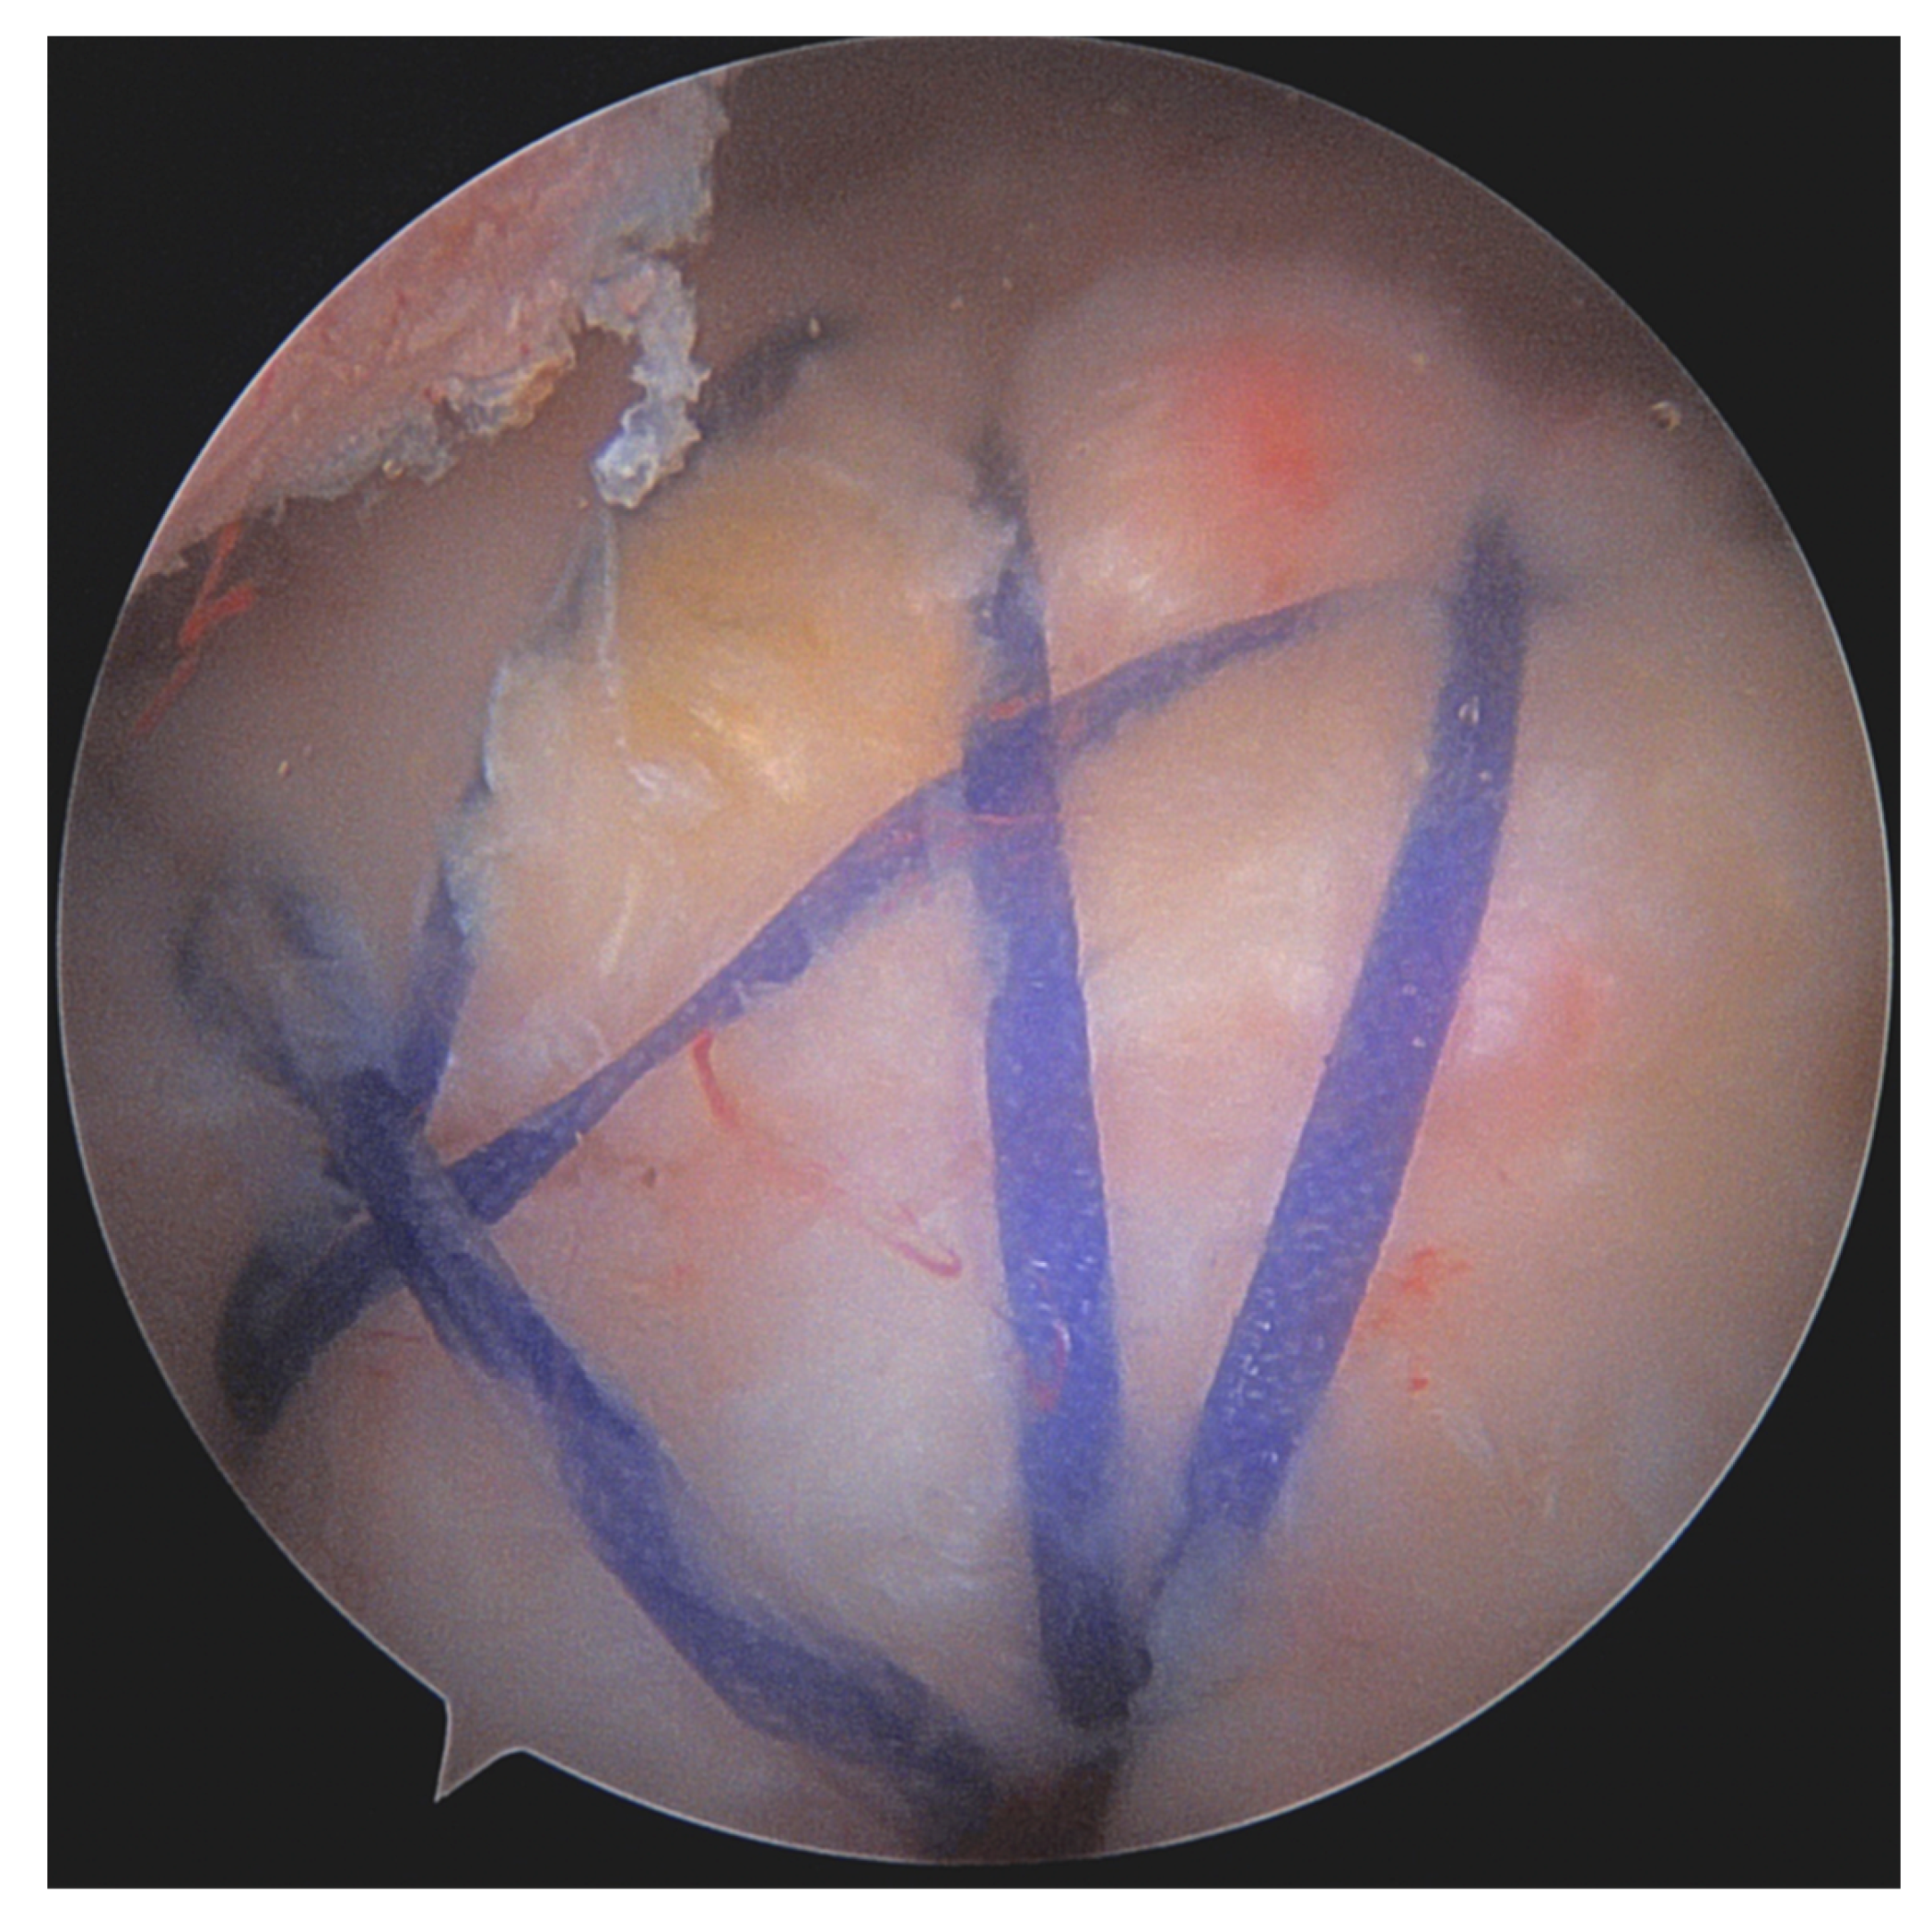

- Burkhart, S.S.; Athanasiou, K.; Wirth, M.A. Margin convergence: A method of reducing strain in massive rotator cuff tears. Arthrosc. J. Arthrosc. Relat. Surg. 1996, 12, 335–338. [Google Scholar] [CrossRef] [PubMed]

- Burkhart, S.S. The principle of margin convergence in rotator cuff repair as a means of strain reduction at the tear margin. Ann. Biomed. Eng. 2004, 32, 166–170. [Google Scholar] [CrossRef]

- Burkhart, S.S.; Danaceau, S.M.; Pearce, C.E. Arthroscopic rotator cuff repair: Analysis of results by tear size and by repair technique-margin convergence versus direct tendon-to-bone repair. Arthroscopy 2001, 17, 905–912. [Google Scholar] [CrossRef]

- Kim, K.C.; Shin, H.D.; Cha, S.M.; Kim, J.H. Repair Integrity and Functional Outcomes for Arthroscopic Margin Convergence of Rotator Cuff Tears. J. Bone Jt. Surg. 2013, 95, 536–541. [Google Scholar] [CrossRef]

- Baumgarten, K.M. Patient-Determined Outcomes After Arthroscopic Margin Convergence Rotator Cuff Repair. Arthrosc. Sports Med. Rehabil. 2020, 2, e517–e522. [Google Scholar] [CrossRef]